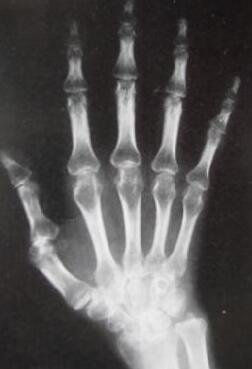

(图:袁女士到院时X光显示风湿症状严重)

4年前,袁女士感到膝盖疼痛,袁女士以为是自己年龄大了,腿不好使了,只是涂了点药膏。两个月后,膝盖突然剧痛,半个多小时都站不起来,经过X线检查,发现袁女士的膝盖,手指关节骨间隙出现了问题,在经过类风湿因子和血沉的进一步检查,最后确诊是类风湿性关节炎。在往后的治疗中,袁女士也是靠药物来止痛,可是疼痛并没有因此而消失,反而一次比一次厉害,最后来到我院风湿专病科室接受治疗。